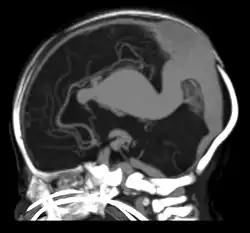

Falcine sinus

A falcine sinus is a venous channel that lies within the falx cerebri connecting the vein of Galen and the posterior part of superior sagittal sinus.[1] It is normally present during fetal development and involutes after birth. The presence of a falcine sinus has been associated with a vein of Galen malformation and other vascular anomalies. The persistence of a falcine sinus after the neonatal period was previously thought to be rare, but has recently been described to be present in up to 5% of all people,[2][1] appearings in approximately 2.1% of CT examinations of adult patients. Some authors have studied the plexus rather than the sinus, a rare form of the venous pathway between the layers of the cerebral falx, which connects the superior sagittal sinus with the inferior sagittal sinus and the straight sinus.[3]